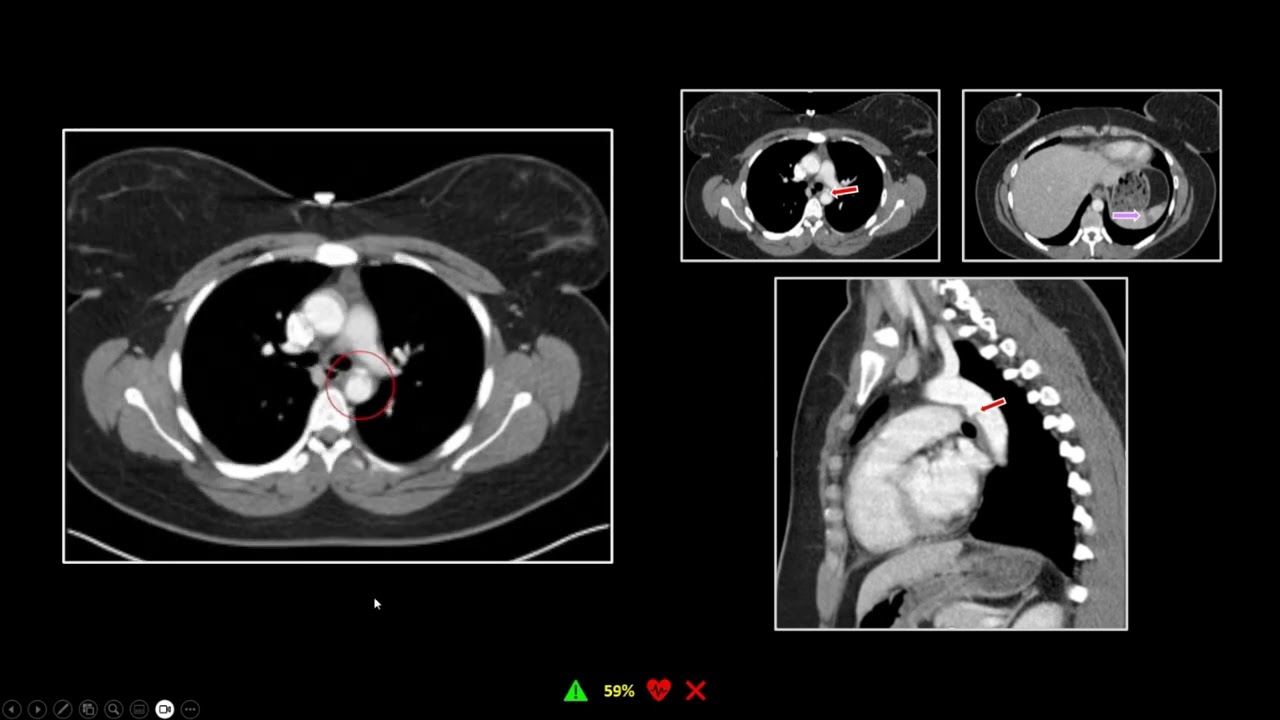

Thoracic Trauma CT: Part 1 (Aorta) | Free Radiology CME

1. Learn the importance of aortic evaluation in trauma imaging.

2. Understand the implications of microembolic phenomena in the solid abdominal organs in cases of thoracic trauma.

3. Learn the specific potential diagnoses associated with retrograde renal contrast opacification.